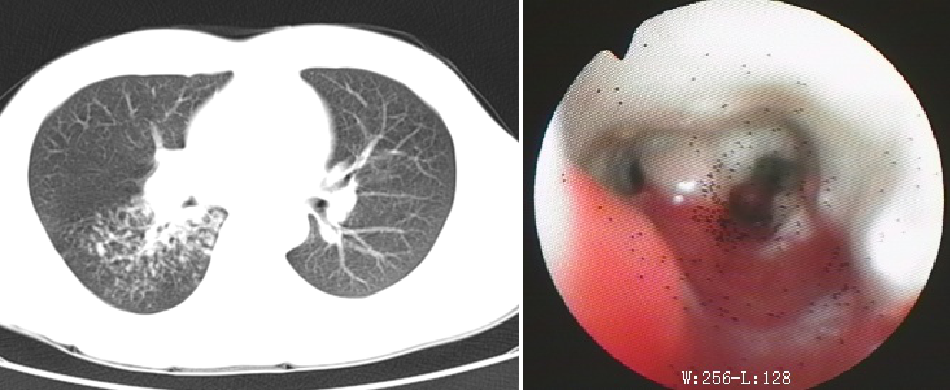

4. 气管、支气管结核:气管及支气管结核主要表现为气管或支气管壁不规则增厚、管腔狭窄或阻塞,狭窄支气管远端肺组织可出现继发性不张或实变、支气管扩张及其他部位支气管播散病灶等。

病原学检测首先需要对选择合适的检测标本,对于肺结核来说,简单易行的标本即为痰标本,可以为咳出的合格痰标本,如无痰,可采用高渗盐水雾化诱导痰。而对于婴幼儿或儿童,鉴于无法采集痰标本或支气管灌洗液,推荐采集胃液标本。对于确实无法留取痰标本的患者,同时鉴于痰标本阳性率相对偏低,对于痰标本阴性的患者,可使用侵入性采集技术获取标本,如支气管镜检查、细针穿刺、肺活检组织标本进行相关病原学检测。